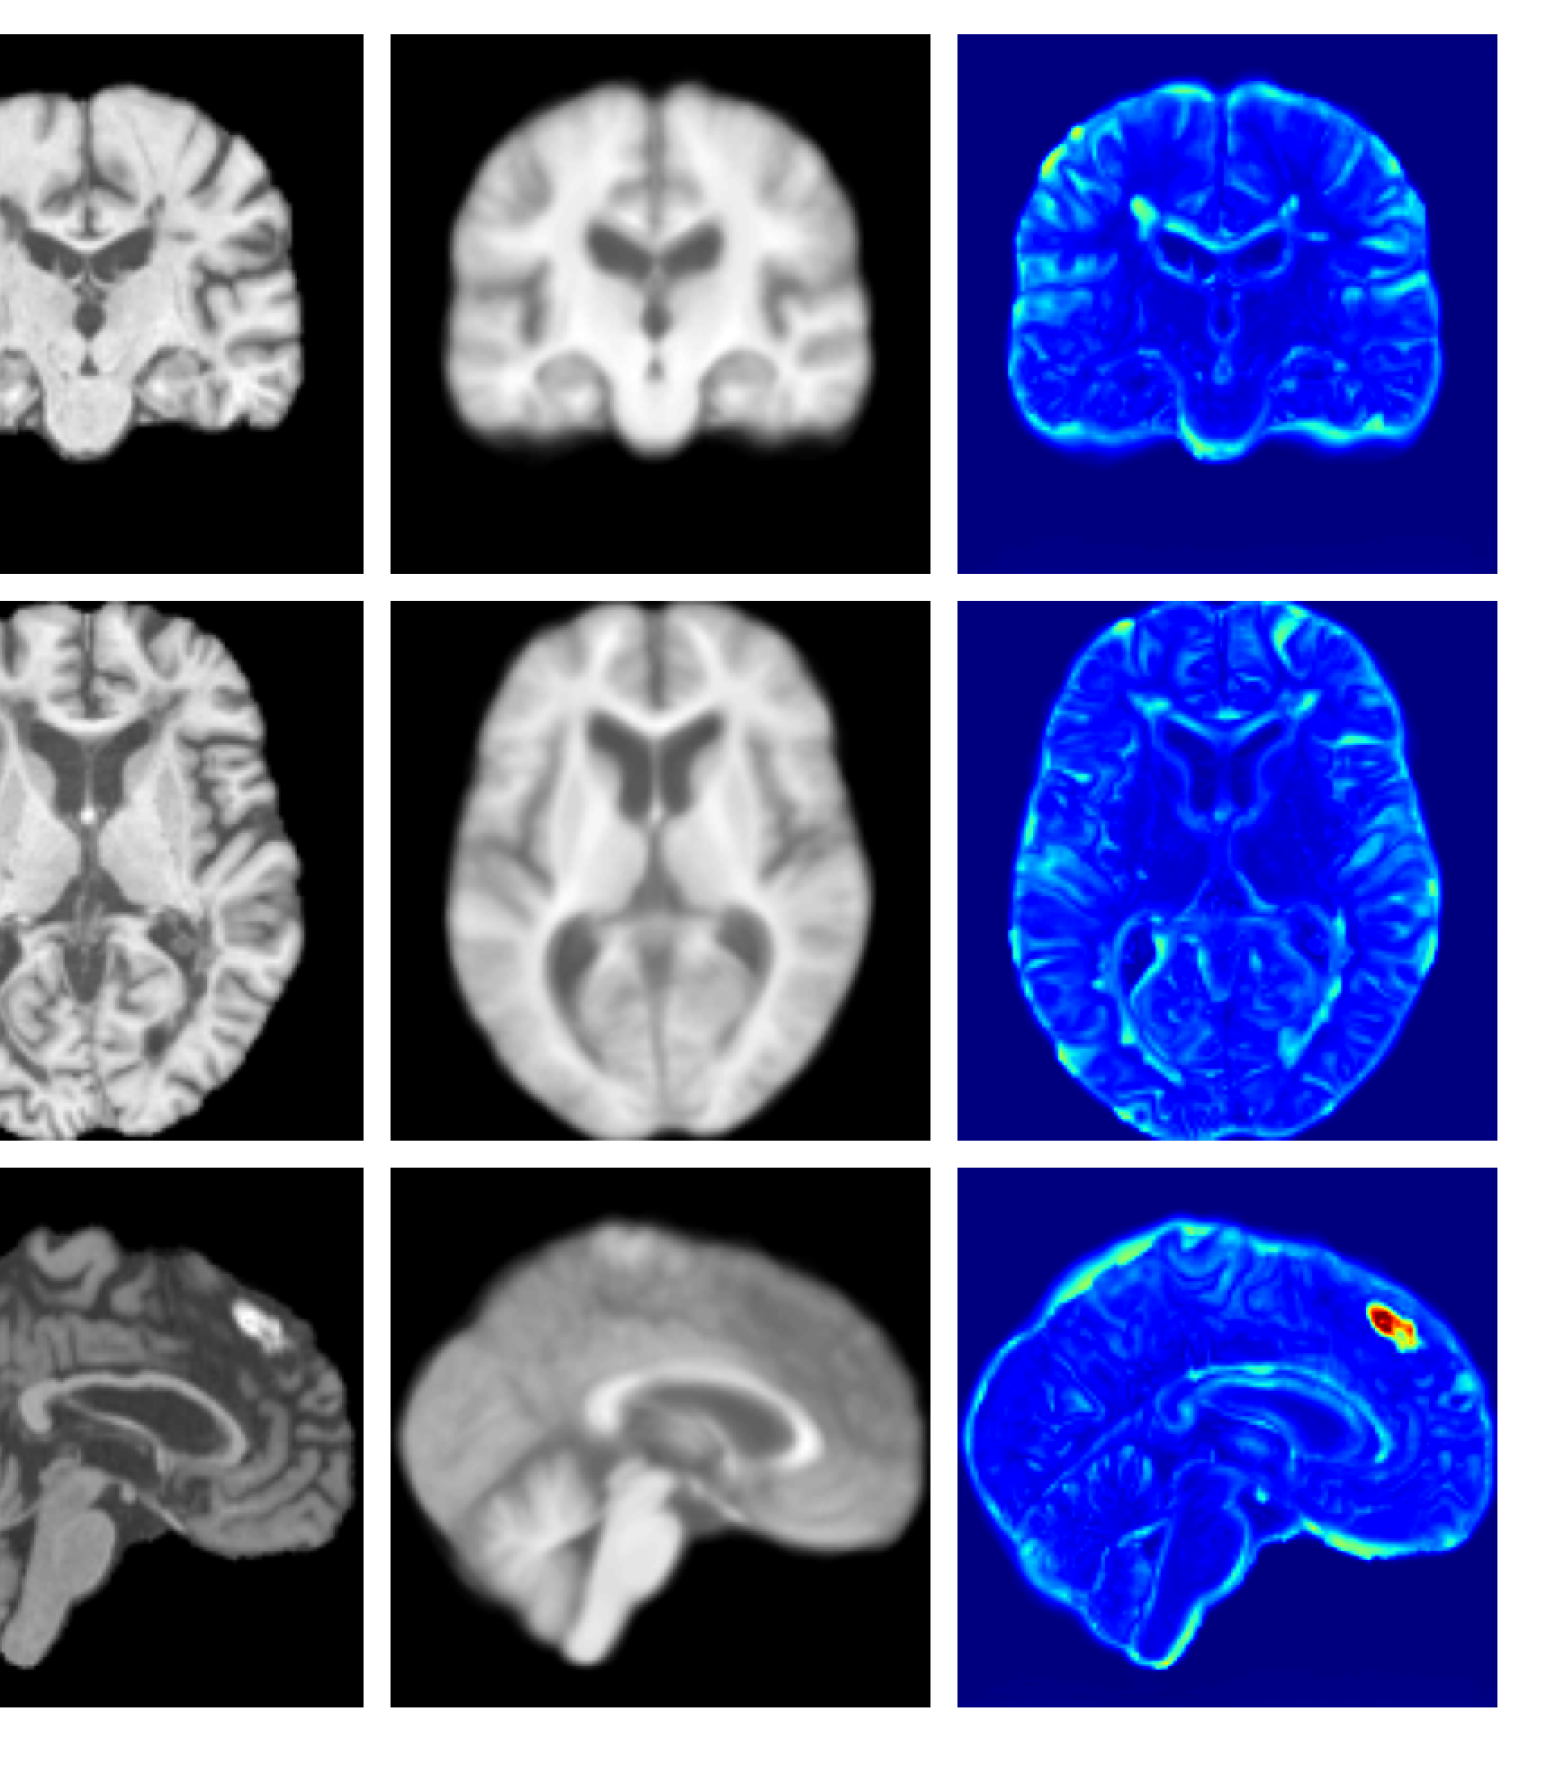

Figures 8 and 9 are enlarged versions of Figures 3 and 4 respectively, with the latter now including results from all compared methods. Figure 10 provides example reconstructions and anomaly maps for an AD subject from the ADNI disease cohort.

Refer to caption

Figure 10: Example reconstructions and anomaly maps for an AD sample from the disease cohort of the ADNI dataset. We expect to see some inpainting of atrophied tissue whilst retaining the defining characteristics of the individual sample.